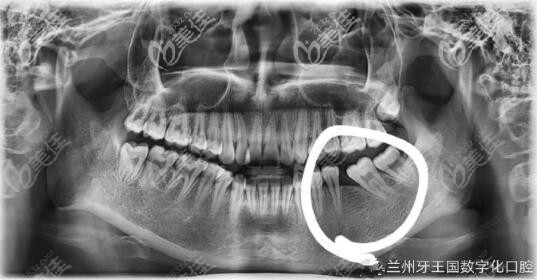

缺牙除了做種植牙之外,開(kāi)可以做正畸關(guān)閉間隙哦,發(fā)一波我在蘭州牙王國(guó)數(shù)字化口腔做自鎖托槽正畸對(duì)比圖,把應(yīng)該拔除的智齒移也到缺牙的位置上,歷時(shí)一年半時(shí)間,這個(gè)時(shí)間花的值不值?

下牙后牙缺失一顆,原本沖著缺牙去醫(yī)院就診,想把缺牙種植,避免鄰牙受影響。蘭州牙王國(guó)口腔醫(yī)生查看后說(shuō)我下排智齒長(zhǎng)得好,去看正畸醫(yī)生看看能不能把智齒拉往前拉。

其實(shí)自己的牙齒也是有些問(wèn)題,有點(diǎn)咬合太緊,牙王國(guó)正畸醫(yī)生生建議我不進(jìn)行種植,我的智齒是可以充當(dāng)磨牙的,這樣不用擁有一顆假牙了。

歷時(shí)一年半時(shí)間,缺牙縫隙關(guān)住了,牙齒也整齊了,你們說(shuō)我這個(gè)這個(gè)時(shí)間花的值不值?